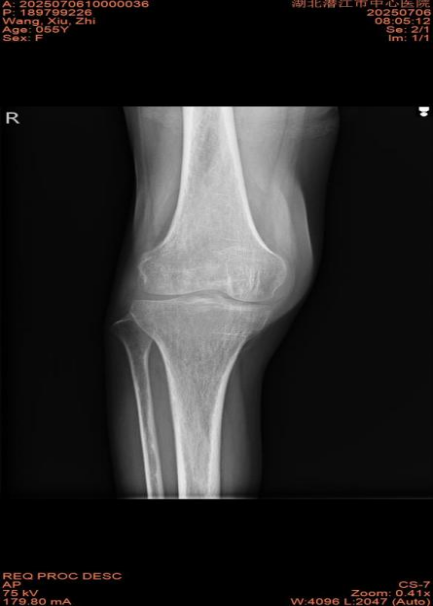

據(jù)了解,王女士飽受右膝關(guān)節(jié)疼痛折磨長達三年,日常行走刺痛難忍,上下樓梯更是困難重重。屋漏偏逢連夜雨,近日一次意外摔倒導(dǎo)致其右膝關(guān)節(jié)腫痛,屈伸活動明顯受限。在家人陪同下,王女士緊急前往潛江市中心醫(yī)院就診。門診X線檢查結(jié)果顯示:“右髕骨骨折,斷端稍有位移”,隨后她被收入骨外科Ⅱ病房,接受進一步的診斷和治療。

入院后,骨外科Ⅱ主任劉興邦、管床醫(yī)生黃大社及其團隊對王女士進行了全面而細致的檢查與評估。結(jié)合王女士長達三年的膝關(guān)節(jié)炎病史及此次新發(fā)的髕骨骨折,專家團隊確診其符合全膝關(guān)節(jié)置換術(shù)的指征,并建議實施該手術(shù),以徹底解決疼痛和功能障礙問題。面對王女士及其家人對手術(shù)風險和術(shù)后恢復(fù)的擔憂,劉興邦主任團隊耐心細致地為患者及家屬講解了手術(shù)原理、成熟流程以及眾多成功案例,并詳細分析了其病情的復(fù)雜性和手術(shù)的必要性。經(jīng)過充分的溝通,王女士最終打消了疑慮,決定接受手術(shù)。